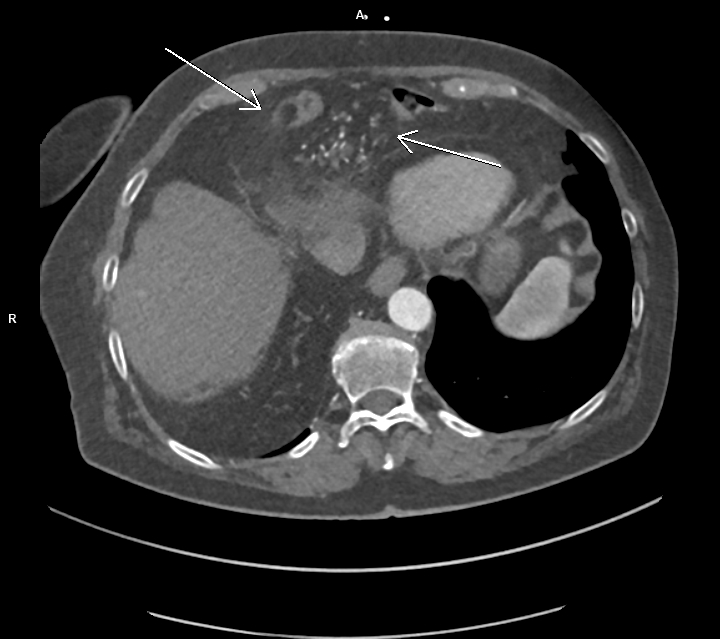

Figurile 3 şi 4: axial CT în timp venos torace şi abdomen superior

Discuţie caz nr 127: se evidențiază hernierea intratoracică a jumătății distale a colonului ascendent, unghiului hepatic al colonului și a unei părți din colonul transvers printr-un orificiu herniar situat anterior de partea dreapta împreună cu o parte din mezocolon.

DE LUAT ACASĂ!!! Hernia Morgagni este una dintre herniile diafragmatice congenitale și este caracterizata de hernierea prin foramenul Morgagni. În comparație cu herniile Bochdalek, herniile Morgagni tind să fie: localizate anterior, mai des pe partea dreaptă ( aproximativ 90%), mici, rare aproximativ 2% din herniile diafragmatice congenitale), cu risc scăzut de prolaps.